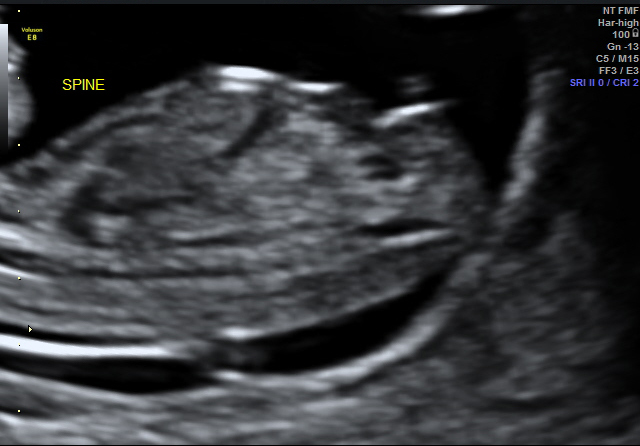

I don't have a complete shot head to toe of baby with nub exposed but I do have a close up... All guesses appreciated!